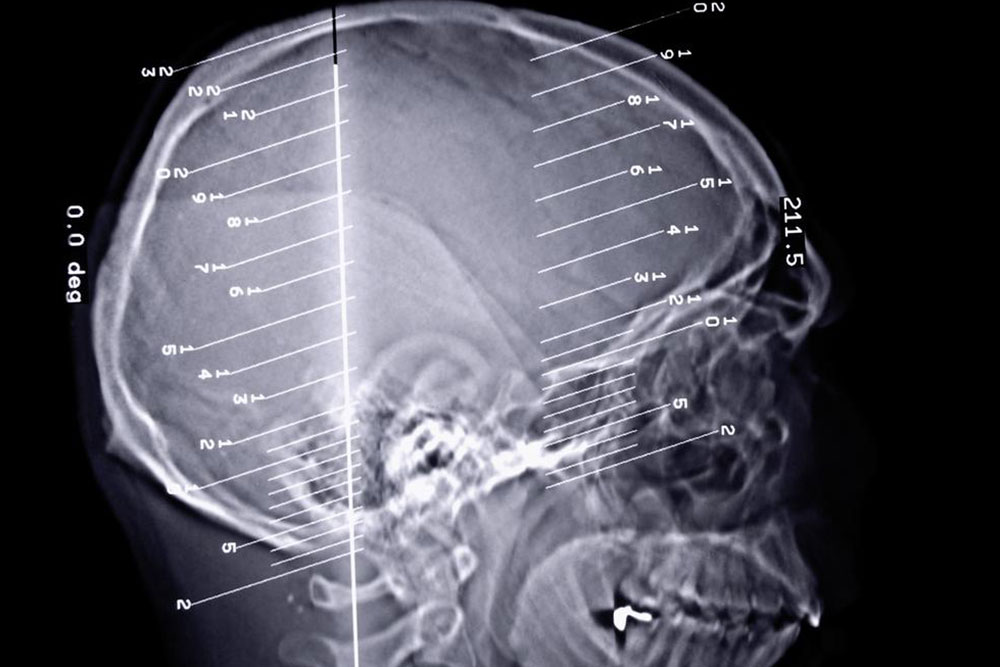

Epilepsy is a dreaded disorder, especially since it is connected to the dysfunctioning of the brain. The brain plays a pivotal role in the functioning of the human body and any kind of issue can lead to severe complications. The disorder is related to the dysfunctioning of the central nervous system in the brain. When the nerve cells in the brain send out wrong signals to the body, the result may be moderate to severe seizure.